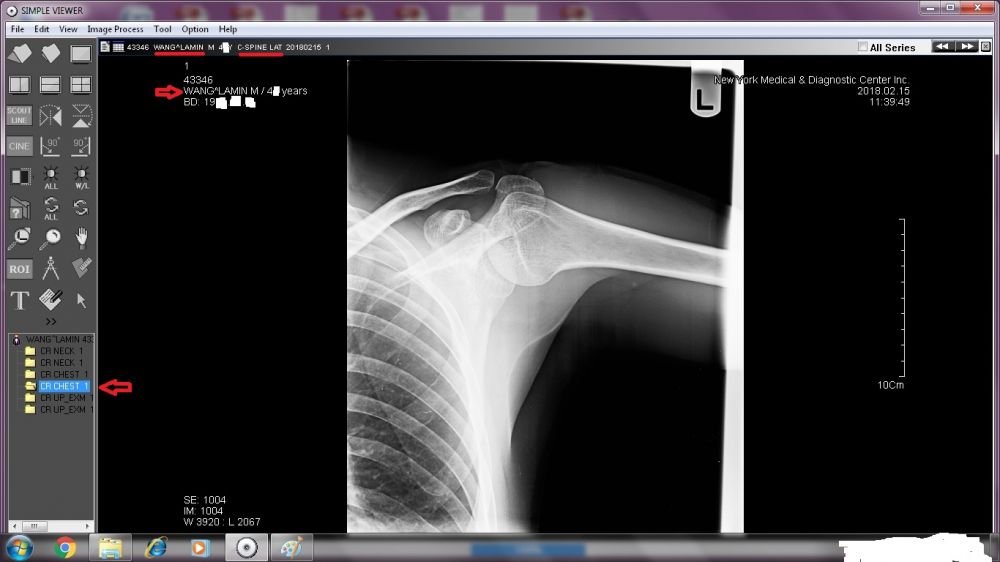

A TREMENDOUS amount needs to be revealed. Right now, I will start with the two sets of X-ray images done by New York Medical & Diagnostic Center (80-46 Kew Gardens Rd, Kew Garden, NY 11415. Tel: (718) 261-1000 ).